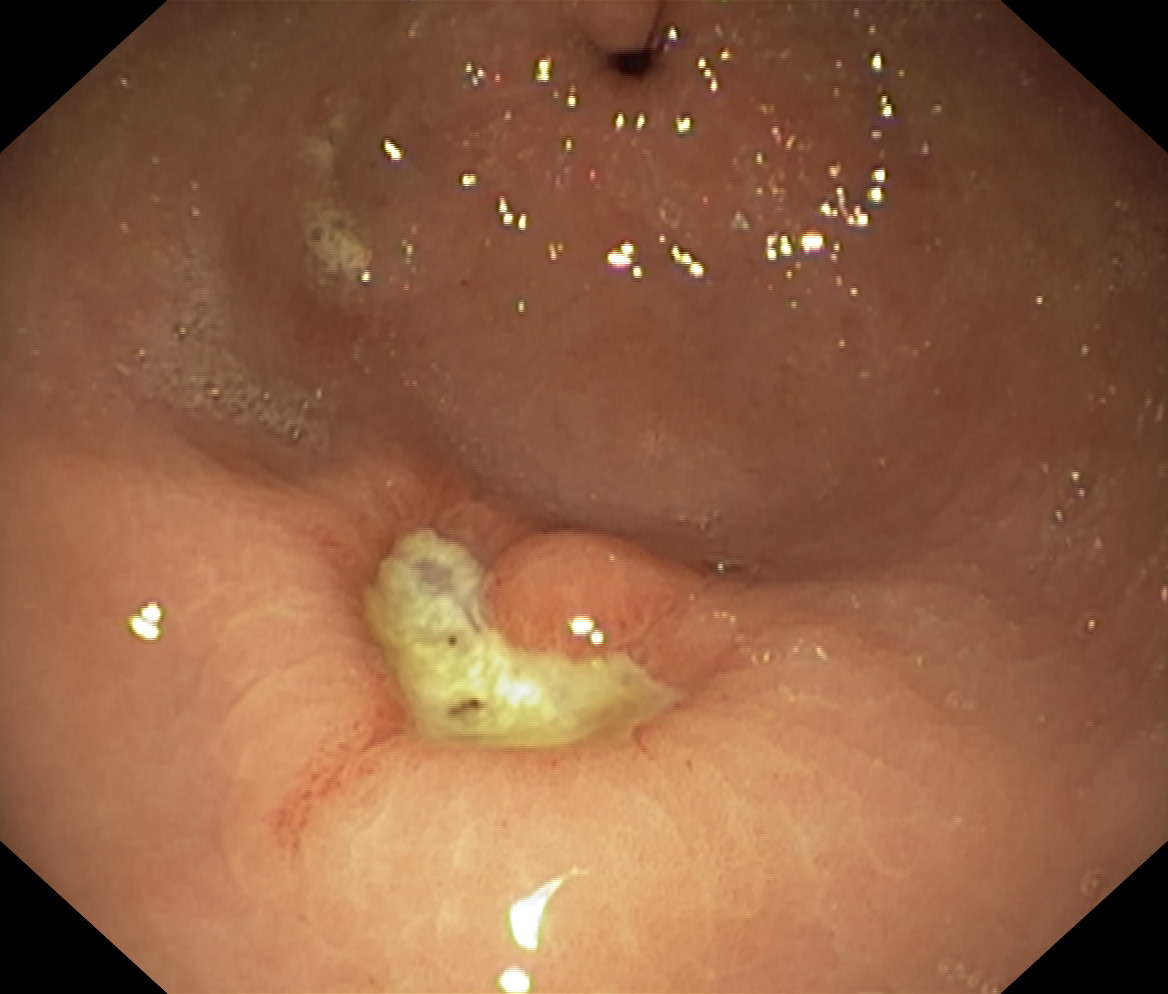

Wrzód trawienny